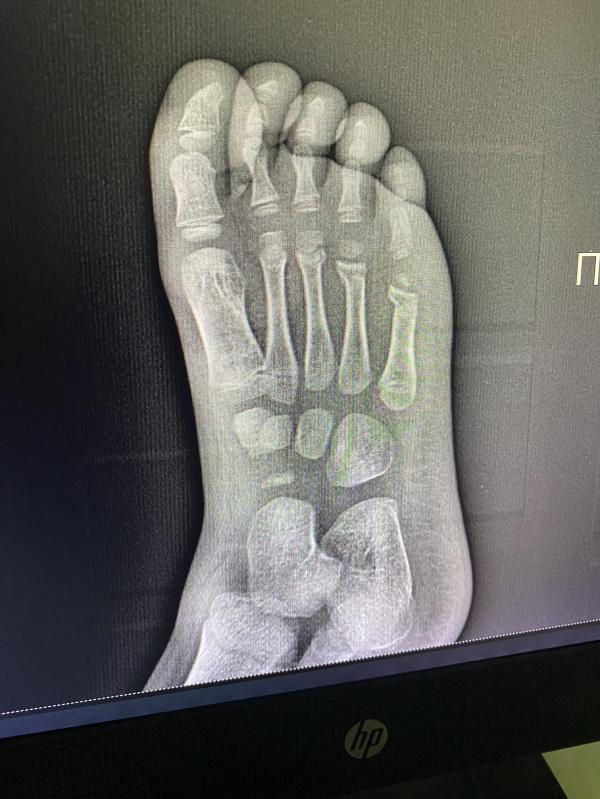

Перелом летом в гипсе: что делать? Совет ортопеда!

post image 2

Добрый день! Есть тут ортопеды? Поставили перелом, я естественно ничего не вижу🙈 и не могу принять эту ситуацию, впереди лето, а нам месяц гипса 😰

Мизинец ?

Под ним